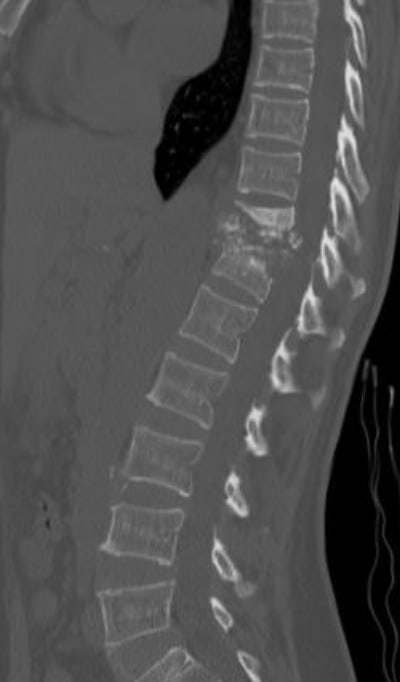

Các hình ảnh sau trích từ CT và MRI của một bệnh nhân lao cột sống.